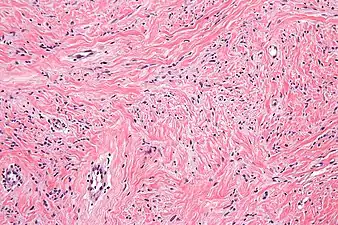

a)Mammary-type myofibroblastoma b) positive for CD34 c) and desmin

a)Mammary-type myofibroblastoma b) positive for CD34 c) and desmin Intermed. mag. Mammary myofibroblastoma

Intermed. mag. Mammary myofibroblastoma High mag. Mammary myofibroblastoma

High mag. Mammary myofibroblastoma

Medical imaging may suggest but cannot prove that a tumor is MFB. Mammography, computed tomography scans, and magnetic resonance imaging of mammary[1][12] and extramammary[1][13] MFB typically show well-defined and well-circumscribed tumors which in almost all cases have no calcifications; these results suggest that the tumor is not malignant but do not indicate which type it might be. The diagnosis of MFB depends on the microscopic histopathology (i.e. appearances after proper tissue preparation and staining) of its pre-surgery biopsied issues. As shown in the upper image and the two images in the Additional images section seen below, both mammary and extramammary MFB tissues contain spindle cells, variable numbers of adipocytes (i.e. fat cells) and broad sheets or, less often, thick bundles of collagen fibers.[5] About 4% of cases have an epithelial tumor cell-like morphology,[5] i.e. the tissues are composed predominantly of epithelioid cells variably mixed with a minority (10% to 40%) of round, polygonal, and spindle-shaped cells.[19] Unlike malignant tumors, MFB tumors do not have: a) atypical cells except in the rare cases which contain small clumps of multinucleated cells; b) rapidly proliferating cells as defined by measuring the proliferative index (i.e. fraction of cells undergoing mitosis); or c) areas of necrosis (i.e. areas of dead or dying cells).[16] Microscopy of tumors in the spindle cell lipoma tentative variant of MFB show a mixture of mature fat cells, ropey collagen, and spindle cells in a myxoid (i.e. background connective tissue that stains blue or purple rather than the red of normal connective tissue) matrix.[18] The blood vessels in these tumors often appear hyalinized.[16] Tumor tissues in the tentative cellular angiofibroma variant of MFB contain spindle cells in all cases, fat cells in ~50& of cases, mast cells, peri-vascular infiltrates of lymphocytes, pleomorphic cells in some cases, and cells with some features of the malignant sarcoma cells in sarcoma tumors in rare cases. (The presence of these sarcoma-like cells does not seem to impact the prognosis of this variant.) All of these cells are in edematous-to-fibrous stromatous tissue.[16]